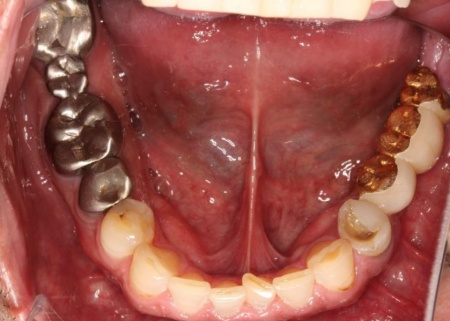

拝見したところ、右上奥歯4本が欠損しており、その影響で全体の噛み合わせのバランスが崩れていました。

さらに、劣化してうまく適合していない被せ物、詰め物、既存のインプラントが複数見られ、これらも噛み合わせを乱す原因となっていました。

他院で治療を行った左下奥歯3本のインプラントは、土台をそのまま活かして人工歯だけ作り直し、噛み合わせを調整します。

左下奥歯1本、右下奥歯2本に装着されていた古い被せ物はすべて外し、ジルコニアクラウンと交換しました。

最後に、見た目や噛み合わせに問題がないかを確認し、治療を終了しています。